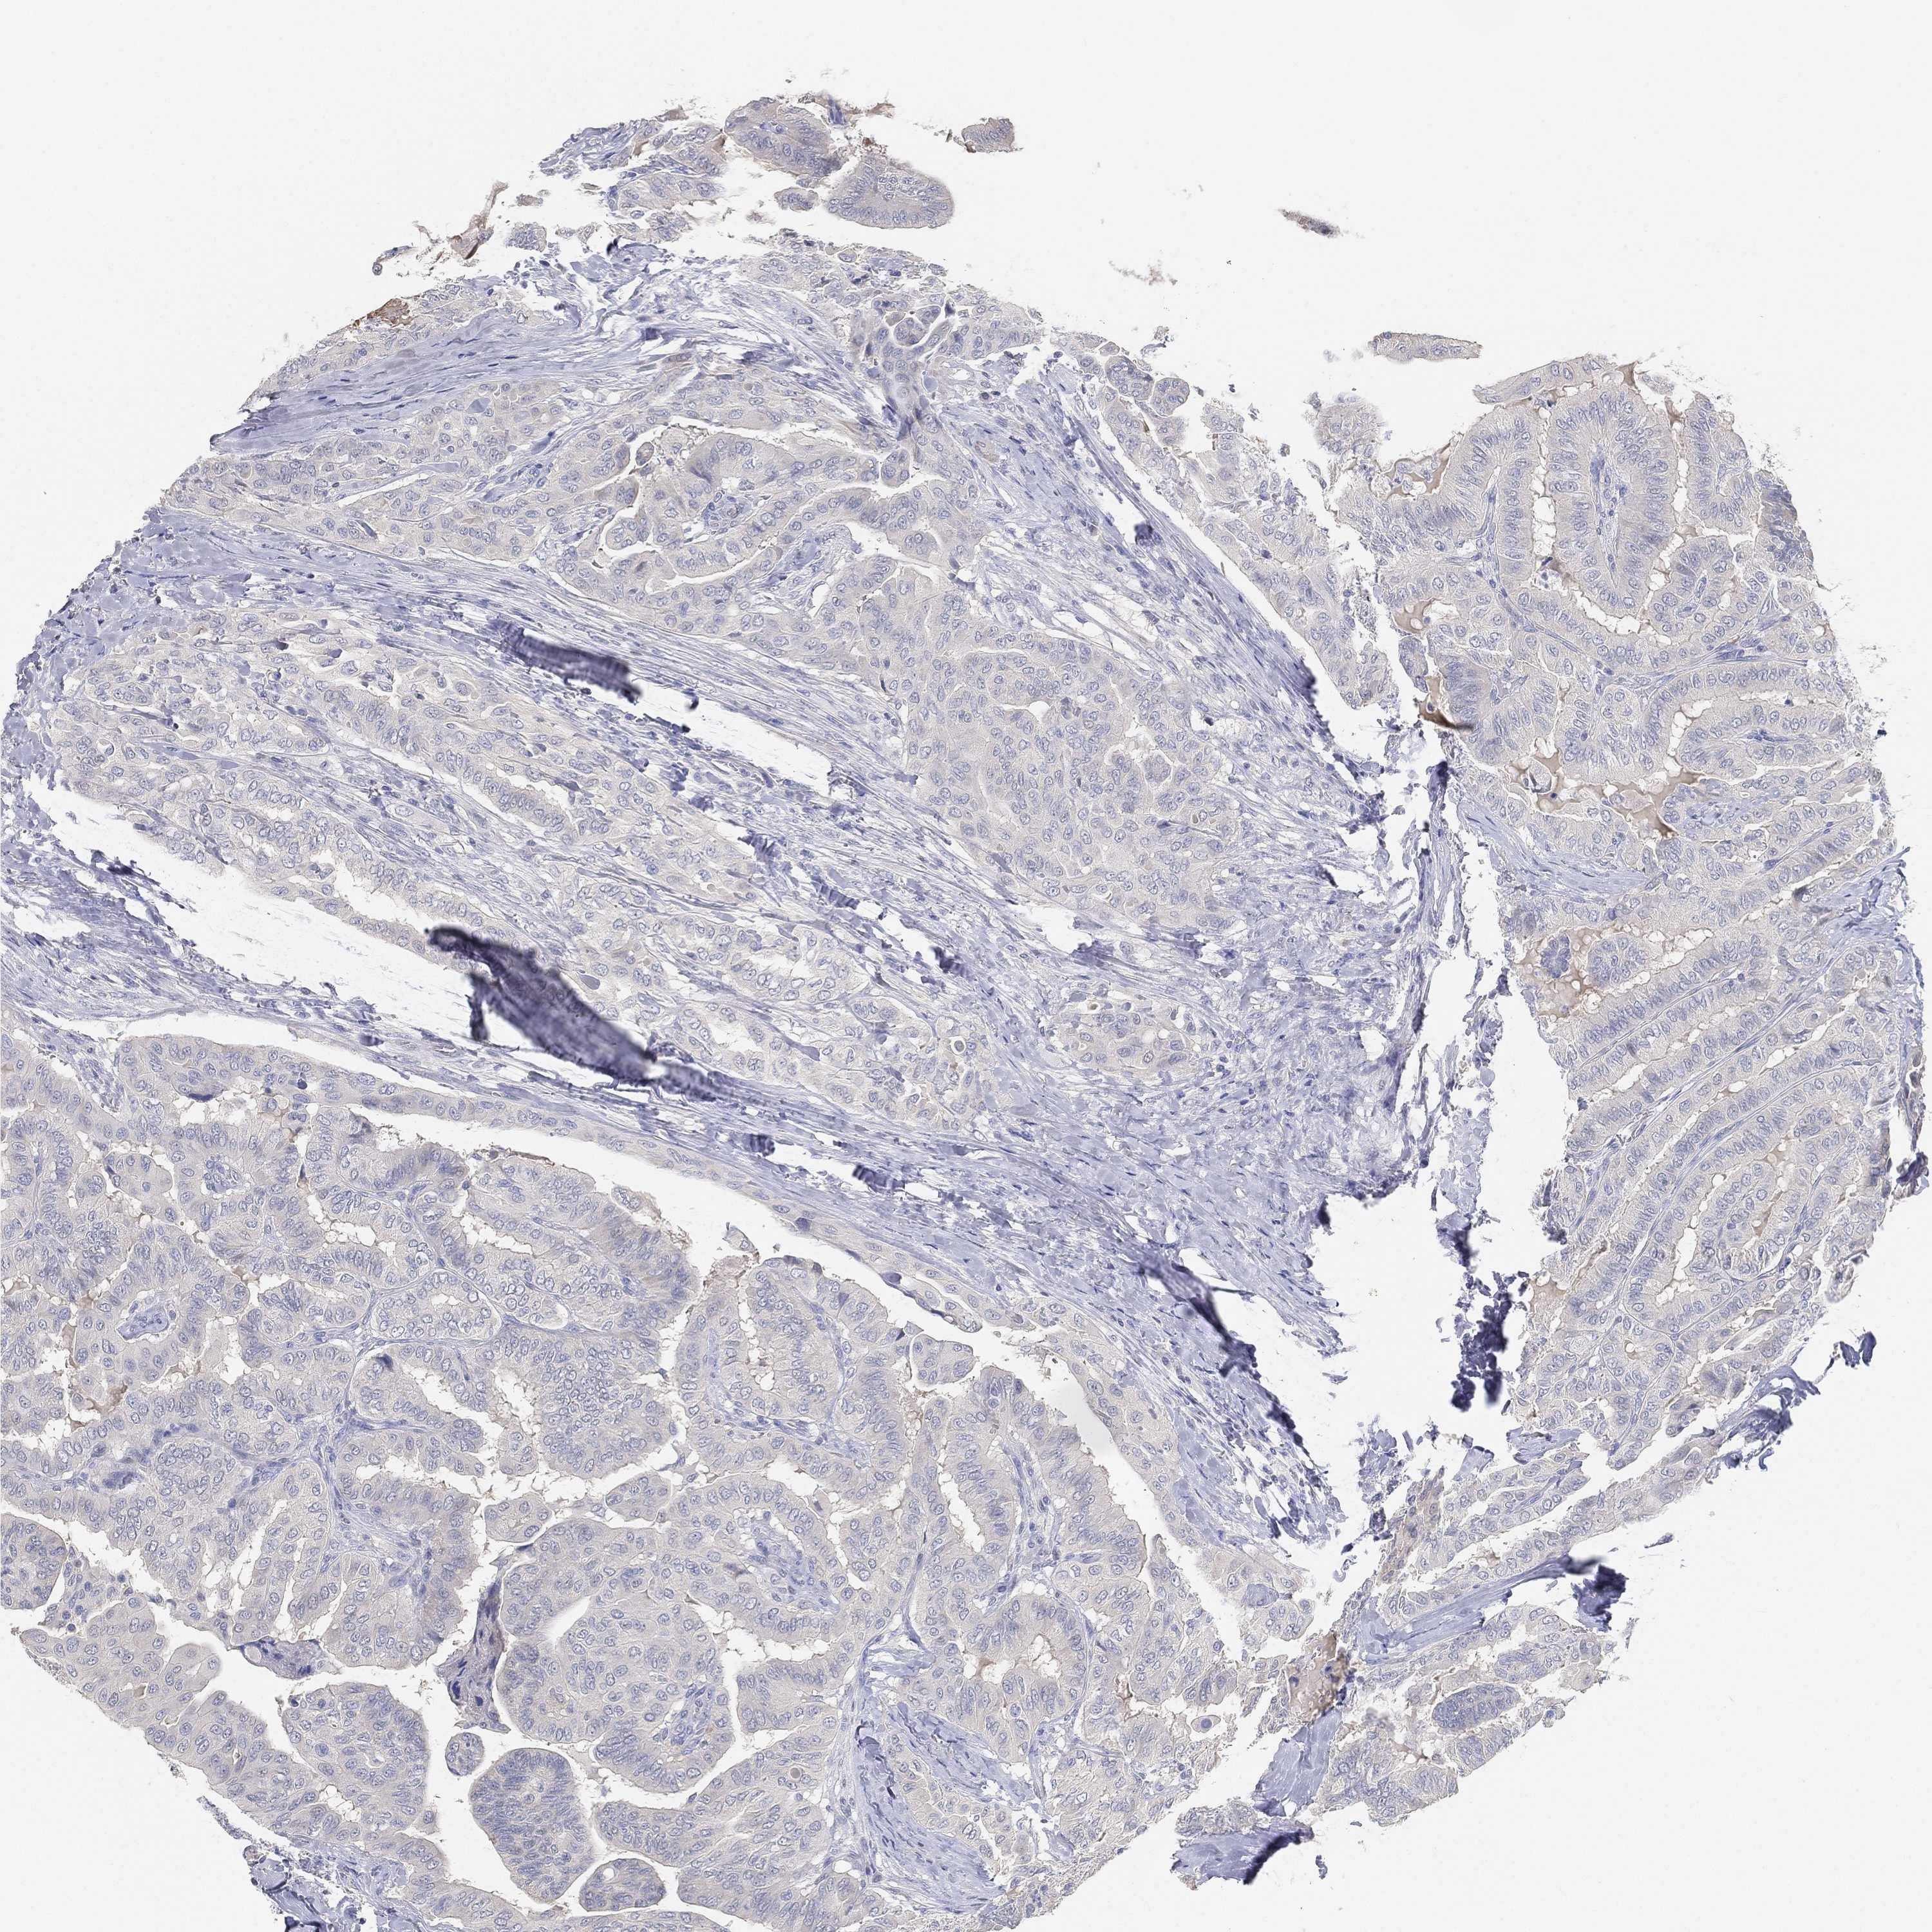

THYROID CANCER - Protein expressioni

A mouse-over function shows sample information and annotation data. Click on an image to view it in a full screen mode. Samples can be filtered based on level of antibody staining by selecting one or several of the following categories: high, medium, low and not detected. The assay and annotation is described here.

Note that samples used for immunohistochemistry by the Human Protein Atlas do not correspond to samples in the TCGA dataset.

Antibody stainingi

Antibody staining in the annotated cell types in the current human tissue is reported as not detected, low, medium, or high, based on conventional immunohistochemistry profiling in selected tissues. This score is based on the combination of the staining intensity and fraction of stained cells.

Each image is clickable and will lead to virtual microscopy that enables deeper exploration of all samples and also displays staining intensity scores, fraction scores and subcellular localization as well as patient and tissue information for each sample.

Antibody HPA007326

Antibody HPA026088

Staining

High

Medium

Low

Not detected

Intensity

Strong

Moderate

Weak

Negative

Quantity

>75%

75%-25%

<25%

None

Location

Nuclear

Cytoplasmic/membranous

Cytoplasmic/membranous,nuclear

Papillary adenocarcinoma, NOS

Follicular adenoma carcinoma, NOS